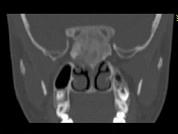

- 单项选择题女,17岁, 鼻阻塞、头痛两年.如图所示符合筛骨病变最可能的诊断是 ( )

B、纤维异常增殖症

E、骨化性纤维瘤